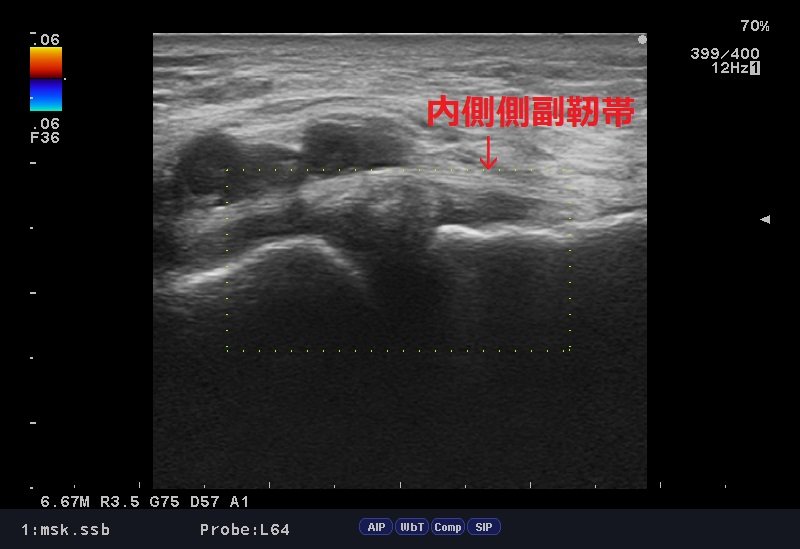

エコー検査では内側側副靭帯周囲、関節内の腫脹が診られ、結果「膝内側側副靭帯損傷」の疑い。

内側側副靭帯損傷2.jpg

ここから早期回復・復帰を目指し、周囲筋、関連筋の緊張を手技でとり、損傷組織の回復をアキュースコープ&マイオパルスで促進させていきます。